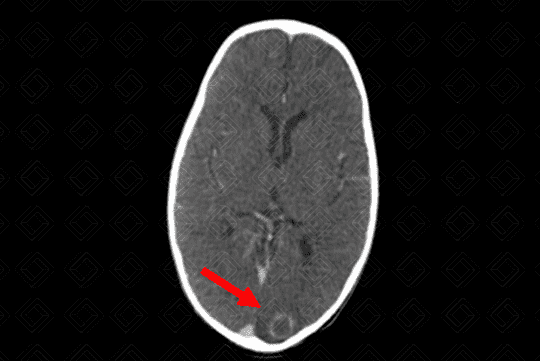

Texto alternativo para a imagem Figura 2. Créditos: Dra Elazir Mota - Rio de Janeiro/RJ

Descrição da lesão (figuras 1 e 2): Abcesso cerebral (tuberculoma). Tomografia computadorizada do crânio com contraste venoso: lesão ovalada, bem definida, hipodensa, com realce periférico pelo meio de contraste (captação anelar) e discreto edema de permeio à lesão, na região occipital esquerda.